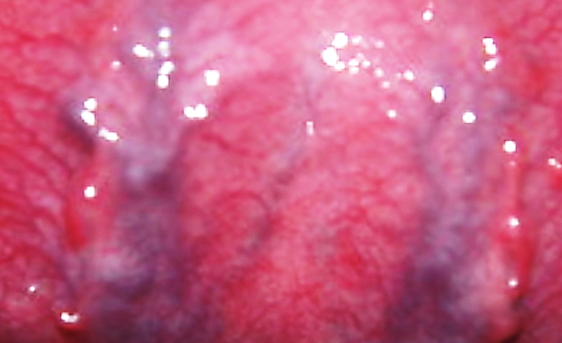

▶ 혀의 색이 보라색 빛이 돌면?

체내에 혈액이 깨끗하지 않다는 혀의 신호이다.

어혈증이 심하고, 혈액순환이 원활하지 않을 수도 있다.

허리, 어깨 통증과 월경이 순조롭지 않을 확률이 높다.